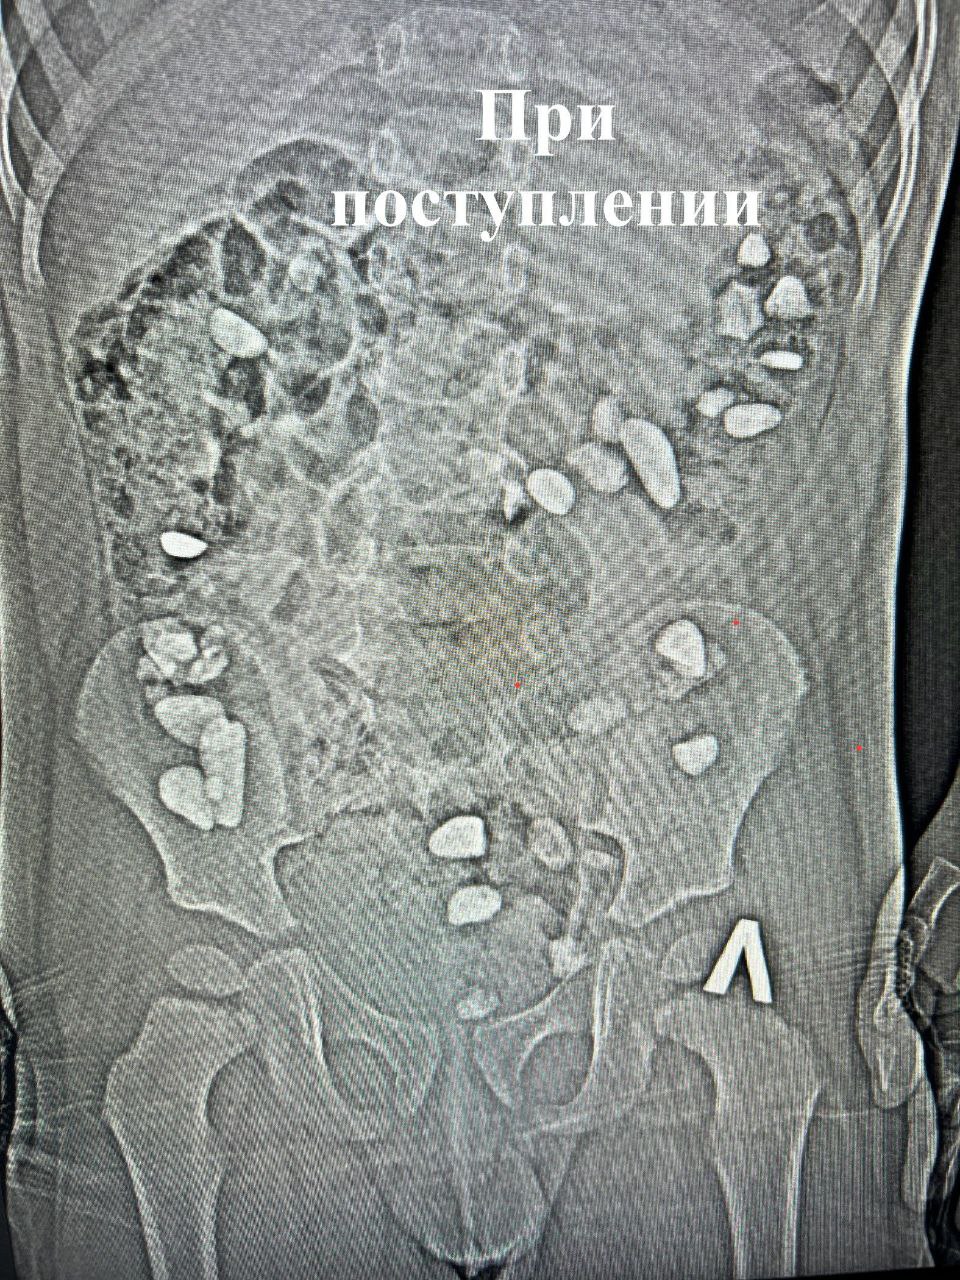

В больницу мальчика доставили с жалобами на боли и вздутие живота. А на рентгене врачи обнаружили в проекции толстой кишки множество инородных тел разного размера. Как оказалось, это были камни. Когда и как ребенок успел их съесть, родители не знают.